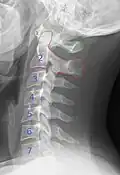

Cervical degenerative changes arise from conditions such as spondylosis, stenosis of intervertebral discs, and the formation of osteophytes. The changes are seen on radiographs, which are used in a grading system from 0–4 ranging from no changes (0) to early with minimal development of osteophytes (1) to mild with definite osteophytes (2) to moderate with additional disc space stenosis or narrowing (3) to the stage of many large osteophytes, severe narrowing of the disc space, and more severe vertebral end plate sclerosis (4).[5][6][7]

X-ray of cervical vertebrae -

X-ray of cervical spine in flexion and extension -